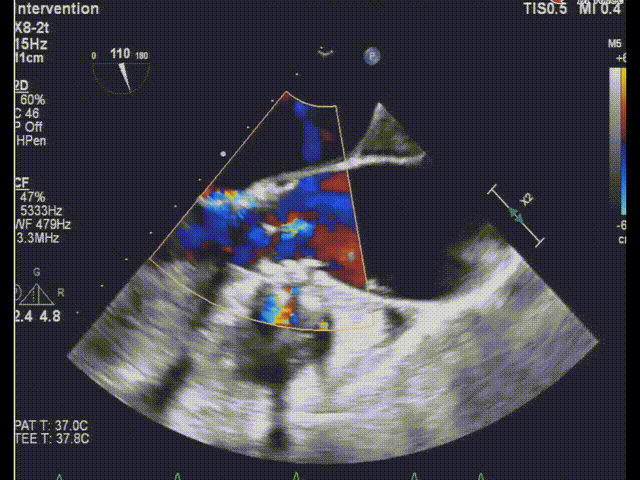

术后食道超声-短轴color

术后食道超声-长轴color